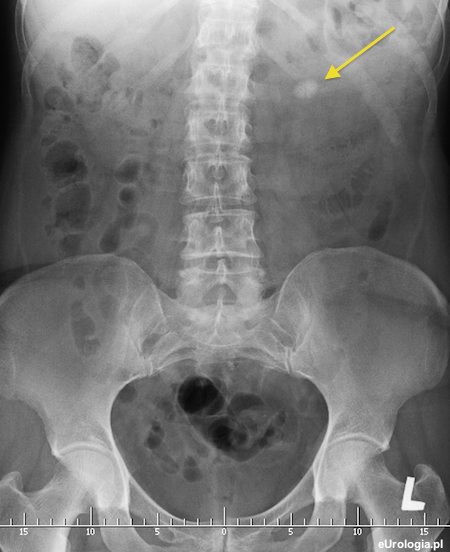

Fot. Zdjęcie przeglądowe z widocznym złogiem średnicy 2 cm w miedniczce lewej nerki.